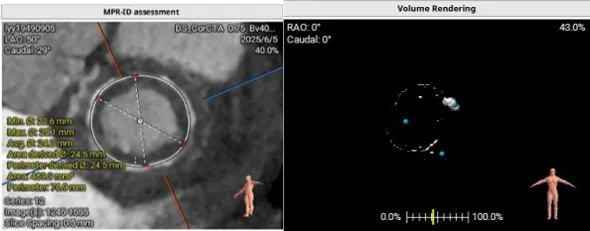

模拟植入26mm的S3瓣膜,评估LVOT阻塞风险:

1.二尖瓣环与主动脉环平面夹角= 128.3°>105°

2.瓣膜与室间隔最短距离= 6.7mm>6mm

3.最小Neo-LVOT面积= 260.4mm2>180mm2

综合评估后LVOT梗阻风险低。